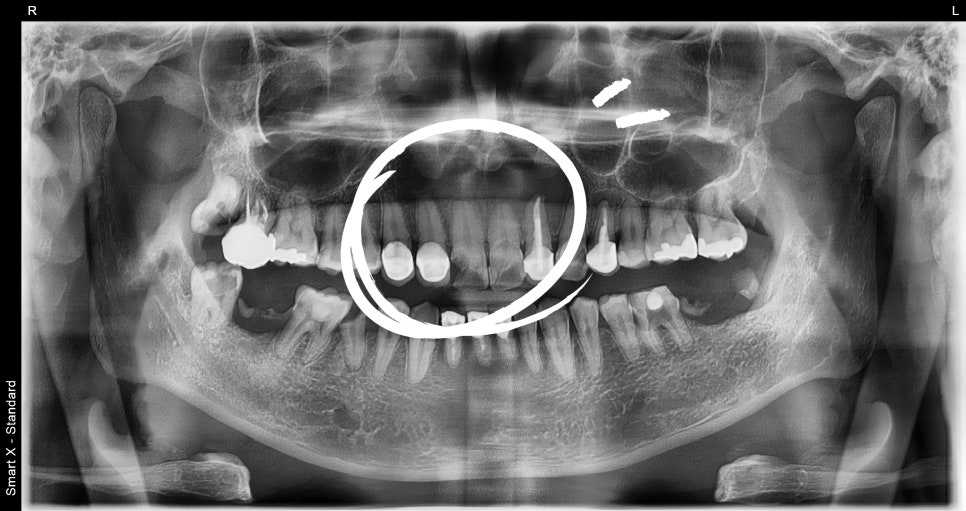

진단 결과: #11번 치아 뿌리에 낭종 확인

단순한 파절로 보였던 앞니 내부를 확인해보니

#11번 치아 뿌리 부위에 큰 낭종(치근단낭종)이 형성되어 있었고,

📸 수술 전

– 치근단 부위에 낭종성 병소